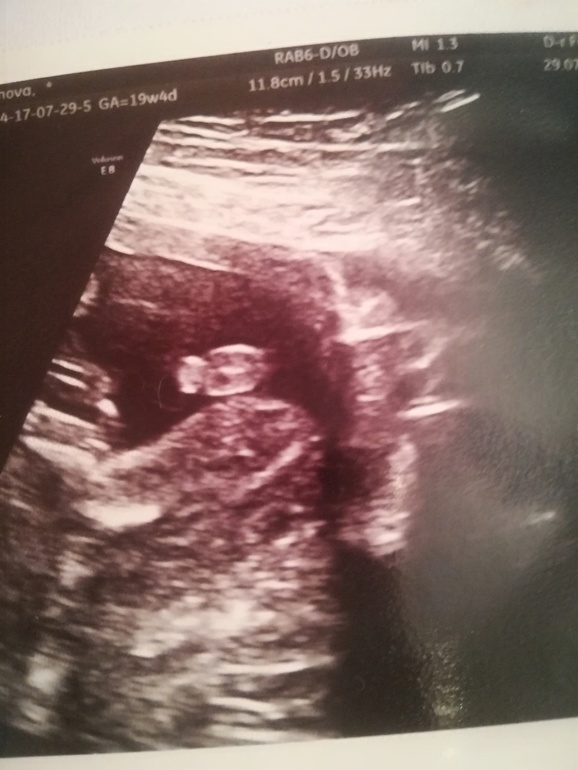

Сегодня, в 19.4 подтвердили мне мальчика)

Вот такая прелесть торчит

Ну если внимательно посмотреть сверху видно вторую ногу.

Врач сказал, что сомнений нет